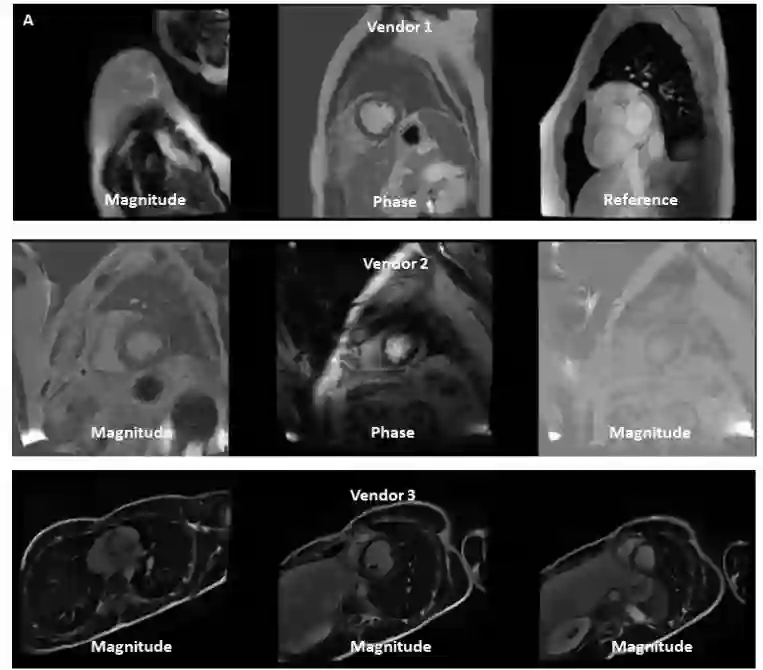

Objectives: To develop an image-based automatic deep learning method to classify cardiac MR images by sequence type and imaging plane for improved clinical post-processing efficiency. Methods: Multi-vendor cardiac MRI studies were retrospectively collected from 4 centres and 3 vendors. A two-head convolutional neural network ('CardiSort') was trained to classify 35 sequences by imaging sequence (n=17) and plane (n=10). Single vendor training (SVT) on single centre images (n=234 patients) and multi-vendor training (MVT) with multicentre images (n = 479 patients, 3 centres) was performed. Model accuracy was compared to manual ground truth labels by an expert radiologist on a hold-out test set for both SVT and MVT. External validation of MVT (MVTexternal) was performed on data from 3 previously unseen magnet systems from 2 vendors (n=80 patients). Results: High sequence and plane accuracies were observed for SVT (85.2% and 93.2% respectively), and MVT (96.5% and 98.1% respectively) on the hold-out test set. MVTexternal yielded sequence accuracy of 92.7% and plane accuracy of 93.0%. There was high accuracy for common sequences and conventional cardiac planes. Poor accuracy was observed for underrepresented classes and sequences where there was greater variability in acquisition parameters across centres, such as perfusion imaging. Conclusions: A deep learning network was developed on multivendor data to classify MRI studies into component sequences and planes, with external validation. With refinement, it has potential to improve workflow by enabling automated sequence selection, an important first step in completely automated post-processing pipelines.